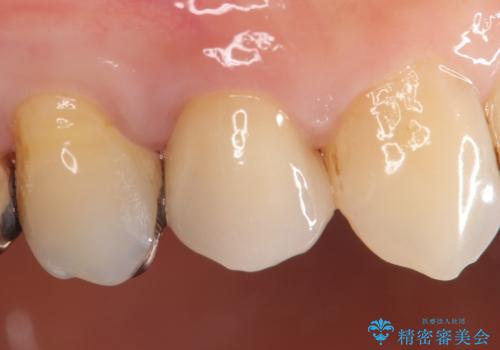

その後オールセラミッククラウン(エクセレント)による補綴を行いました。

前歯の補綴ではオールセラミッククラウンを希望される患者様が多いですが、オールセラミッククラウンの中でも、エコノミー、スタンダード、スペシャル、エクセレントとランクがあります。

その中でも特に審美性が高いのがスペシャル、エクセレントです。スペシャル、エクセレントは口腔内写真をもとに熟練の技工士が、患者様の口腔内に合わせたオーダーメイドのクラウンを製作致します。